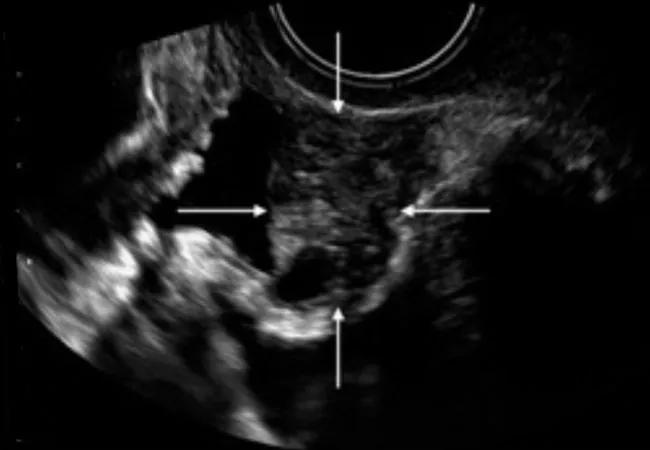

In terms of imaging, ultrasound is the method of choice for UTE. A transvaginal approach is appropriate for bladder DE and a transabdominal for the assessment of suspected ureteral disease. The latter also should be used in cases of ureteral DE to rule out hydronephrosis, which is often asymptomatic.

Transvaginal ultrasound depiction of the bladder. (A) Normal bladder and (BD) three bladder deep endometriosis nodules, identified with white arrows.